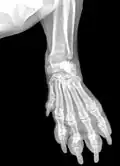

Zdjęcia rentgenowskie przedniej łapy jamnika